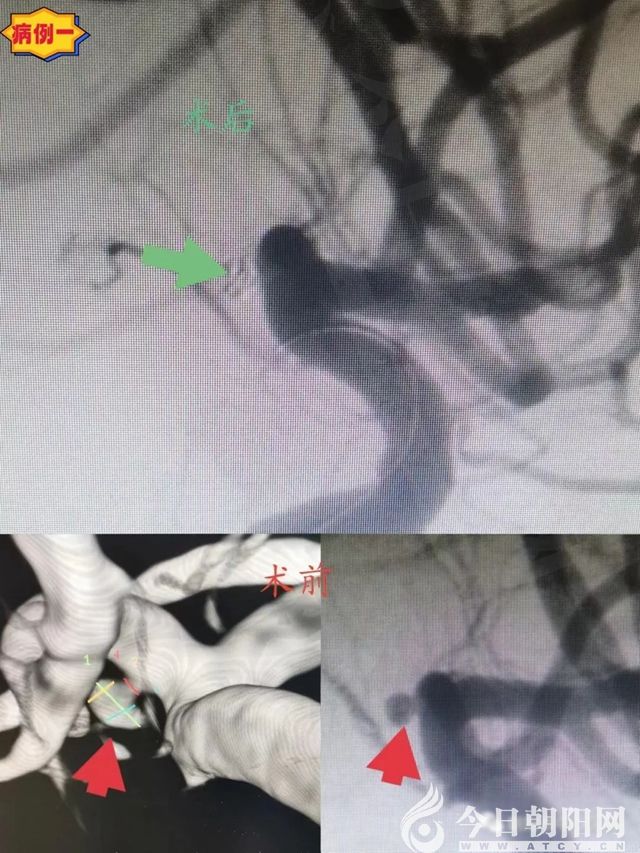

病例一:45歲,女性,以“突發(fā)頭痛伴惡心嘔吐2小時”為主訴入院。平時健康,無基礎病史。查體:GCS評分15分,頸抵抗,無其他神經系統(tǒng)陽性體征。

頭顱CT:彌漫性蛛網膜下腔出血,以環(huán)池及鞍上池為主。DSA:左側大腦前動脈A1段微小動脈瘤,瘤體指向下方,大小約2.08mm×1.6mm。診斷:左側大腦前動脈A1段動脈瘤,自發(fā)性蛛網膜下腔出血。